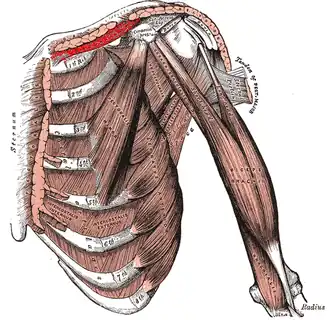

Deep muscles of the chest and front of the arm, with the boundaries of the axilla. (Subclavius visible at upper left, above first rib.) | |

The subclavius is a small triangular muscle, placed between the clavicle and the first rib.[1] Along with the pectoralis major and pectoralis minor muscles, the subclavius muscle makes up the anterior axioappendicular muscles, also known as anterior wall of the axilla.[2]